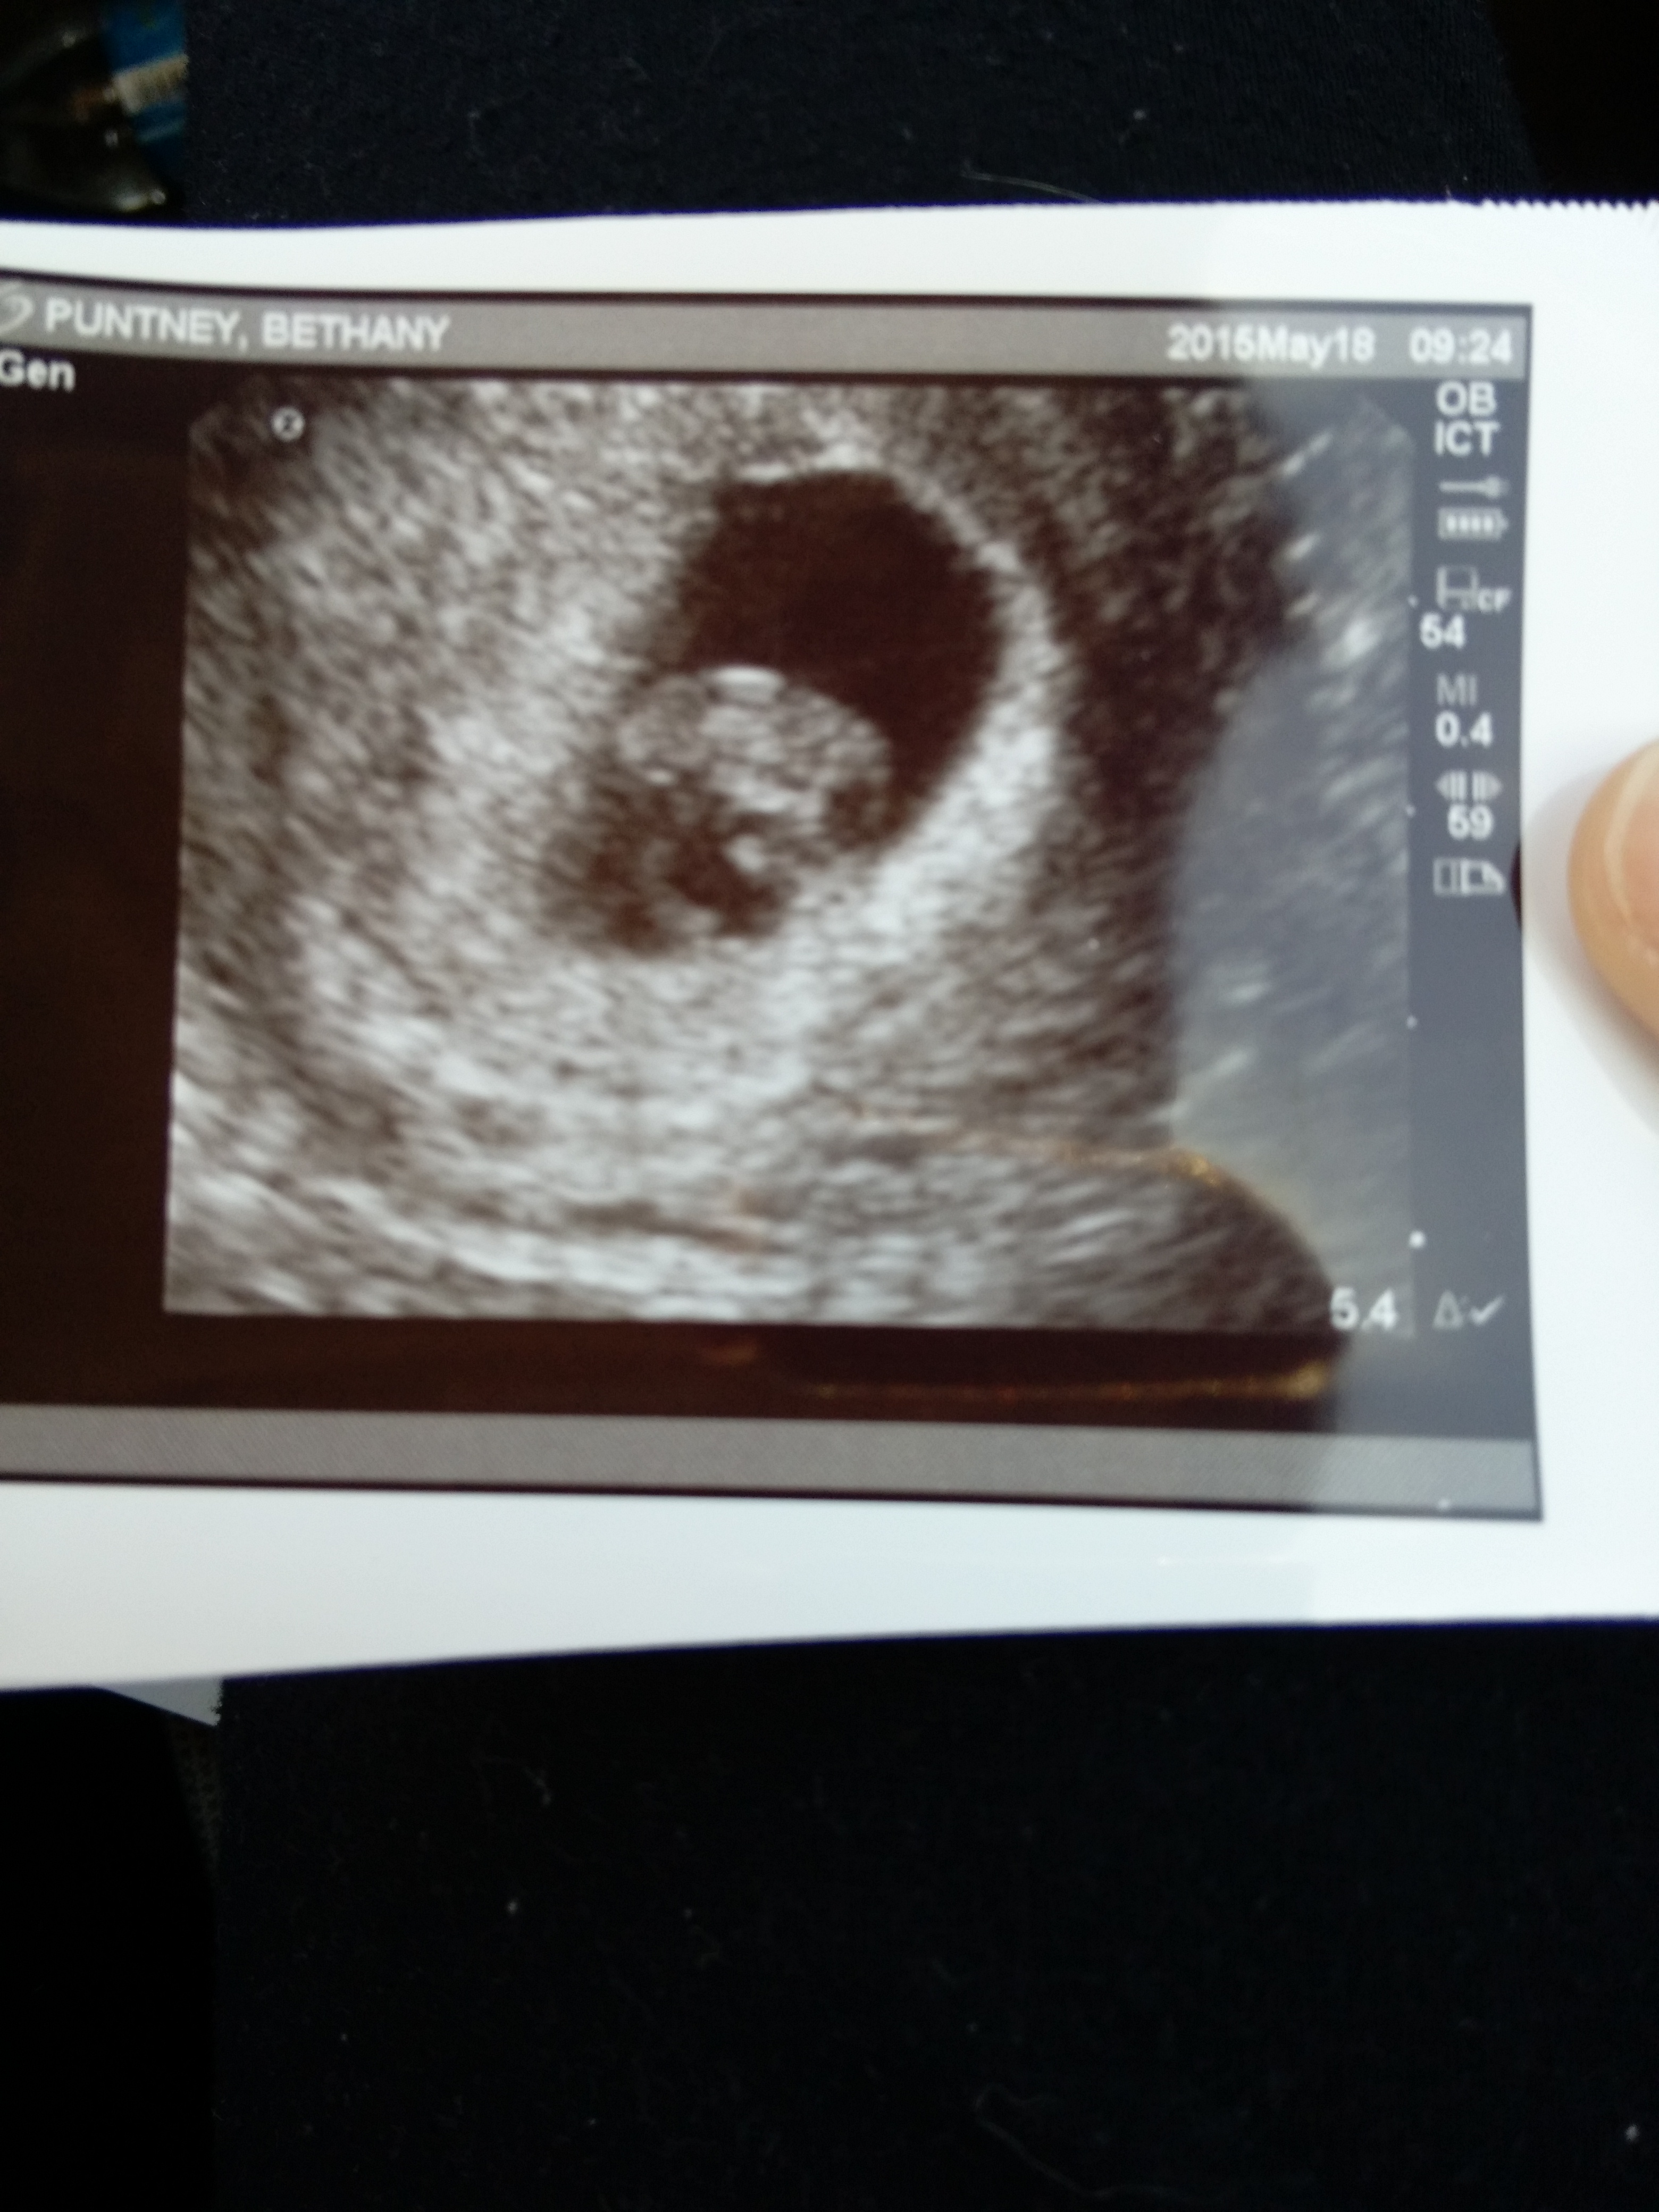

I thought I was 9 weeks today but am actually measuring at 8 weeks 3 days. My OB decided to keep the original due date since it's less than a week difference. Christmas Eve baby!